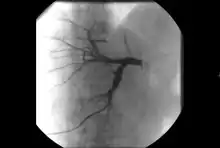

- Angiography: Imaging the blood vessels to look for abnormalities with the use of various contrast media, including iodinated contrast, gadolinium based agents, and CO2 gas.[3]

- Angiography: Sometimes referred to as traditional angiography, catheter angiography or digital subtraction angiography (DSA.) A small needle is inserted into a blood vessel, then exchanged for a catheter over a wire. The catheter is directed at the vessel to be studied, and contrast is directly injected to evaluate the lumen under video X-ray. This is an older technique than modern CT angiography or MR angiography, but provides unique advantages. With a catheter in place, provocative maneuvers can be performed such as breath holds or instillation of vasodilators, to evaluate a patient's blood flow dynamically. This can reproduce symptoms and identify functional abnormalities in a vessel that a static CT or MR imaging cannot.[79][80] Angiography provides the basis for all endovascular therapy.